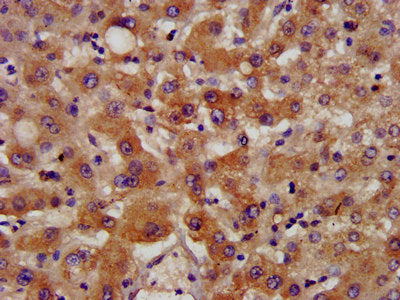

IHC image of NSDHL Antibody diluted at 1:400 and staining in paraffin-embedded human cervical cancer performed on a Leica BondTM system. After dewaxing and hydration, antigen retrieval was mediated by high pressure in a citrate buffer (pH 6.0). Section was blocked with 10% normal goat serum 30min at RT. Then primary antibody (1% BSA) was incubated at 4°C overnight. The primary is detected by a biotinylated secondary antibody and visualized using an HRP conjugated SP system.